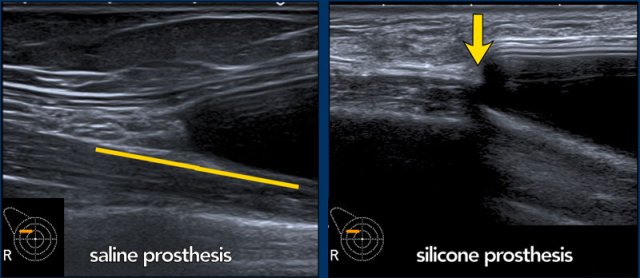

Step off sign

The step off sign is an artefact caused by a lower transmission speed of the ultrasound waves through Silicone ( 970m/sec in Silicone gel and 1540m/sec through water).

As a result the chest wall seems to be deeper at the level of the prosthesis.

This artefact is not seen in saline filled implants.

Here you can see the difference between a saline and a silicone prosthesis.